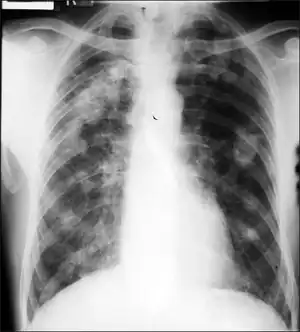

Caplan's syndrome (or Caplan disease or rheumatoid pneumoconiosis[1]) is a combination of rheumatoid arthritis (RA) and pneumoconiosis that manifests as intrapulmonary nodules, which appear homogeneous and well-defined on chest X-ray.[2]

Caplan syndrome is a nodular condition of the lung occurring in dust-exposed persons with either a history of rheumatoid arthritis (RA) or who subsequently develop RA within the following 5–10 years.[3] The nodules in the lung typically occur bilaterally and peripherally, on a background of simple coal workers' pneumoconiosis. There are usually multiple nodules, varying in size from 0.5 to 5.0 cm. The nodules typically appear rapidly, often in only a few weeks. Nodules may grow, remain unchanged in size, resolve, or disappear and then reappear. They can cavitate, calcify, or develop air-fluid levels. Grossly, they can resemble a giant silicotic nodule. Histologically, they usually have a necrotic center surrounded by a zone of plasma cells and lymphocytes, and often with a peripheral inflammatory zone made of macrophages and neutrophils.

- Chest radiology shows multiple, round, well defined nodules, usually 0.5-2.0 cm in diameter, which may cavitate and resemble tuberculosis.